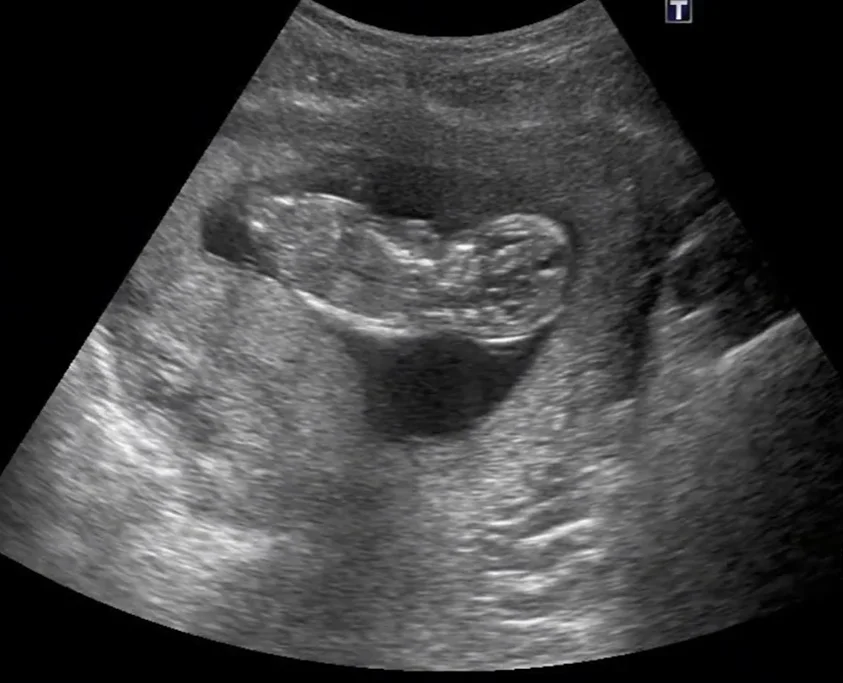

• Khối u phần phụ trong thai kỳ (Adnexal Mass in Pregnancy)

• Nang buồng trứng thai nhi (Ovarian Cyst)